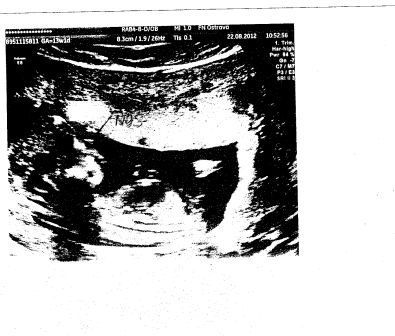

Měříme 8,3cm.Podle ultrazvuku jsme 13+1 takže už II trimestr.

Prcek už je krásně vidět na té fotečce